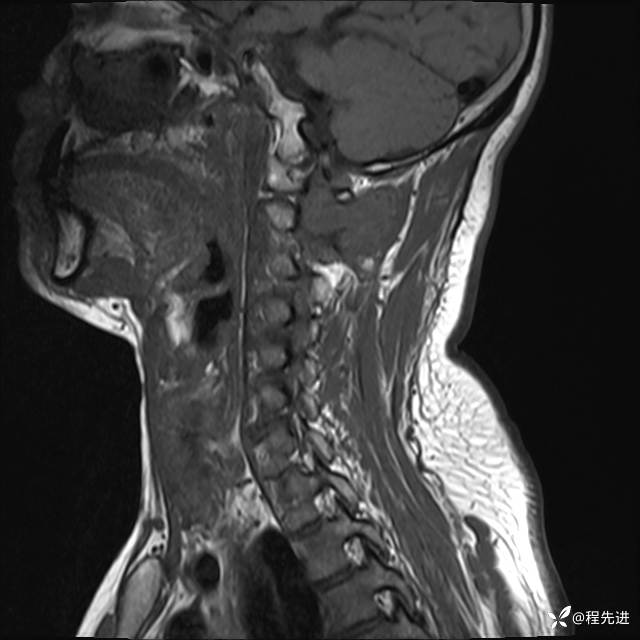

MRI平扫+增强:

T2:

T1: